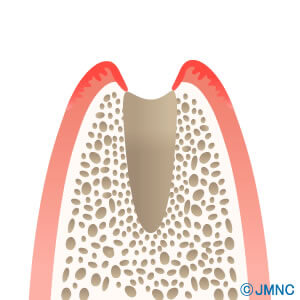

顎骨の量(幅、高さ)が不十分で、通常の方法ではインプラントが埋入できない場合があります。こんな場合、以前はインプラント治療をあきらめなければなりませんでした。しかし技術、材料の発達によって、顎骨を造り出して、インプラントを埋入できるだけの骨量を確保するために、様々な方法が考えられ、確立されてきました。これが骨造成です。患者様自身の、下顎などの豊富にある部分の骨を採取して不足部分に移植する、自家骨移植。骨に置換する人工材料を、不足する部分に補填する方法。両方を混合する方法などがあります。骨が不足し、インプラント治療をあきらめていた方も、一度ご相談ください。

破折したり、虫歯がひどくて抜歯が必要な歯を抜歯していきます。

抜歯した後には、歯の大きさの穴が空きます。ここにインプラントを埋入するための、ドリリングを行います。

インプラントを埋入します。抜歯した穴のほうが大きいため、インプラントと骨との間に、隙間ができます。

インプラントと骨の隙間に、顆粒状の骨補填材を、濃厚血小板、成長因子を含むジェルを混ぜて入れます。その上を、ジェルから作った膜で覆います。

3~4か月で骨とインプラントが生着し、骨補填材も本当の骨に置き代わってきます。